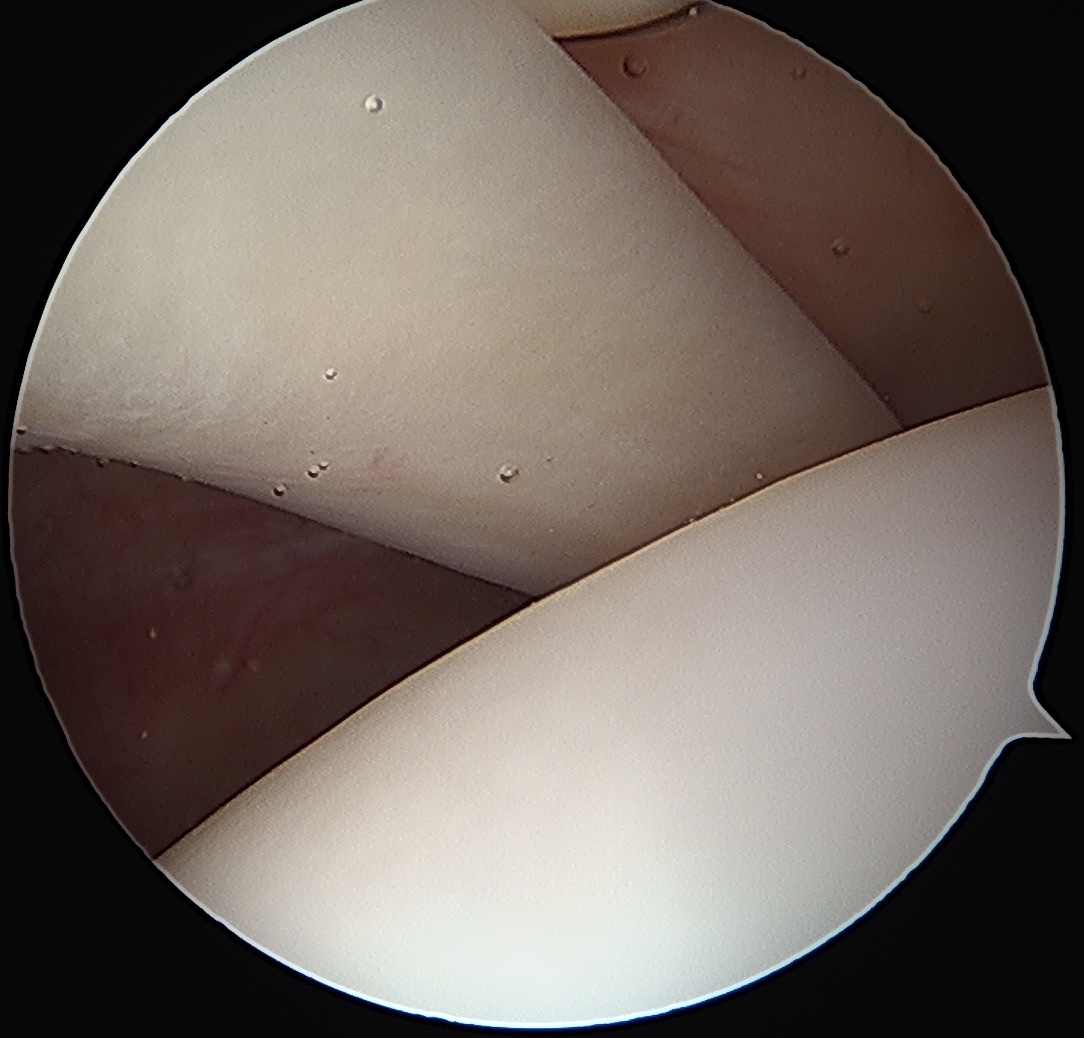

Normal

Tendonopathy

Medial subluxation of LHB